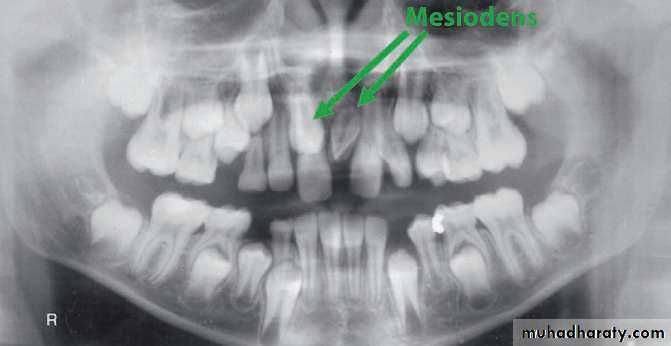

• Mesiodens :When they occur between the maxillary central incisors.

• Common region of the jaws to be affected is the premaxilla.

Mesiodens

Many supernumerary teeth never erupt, but they may delay eruption of nearby teeth or cause other dental problems.